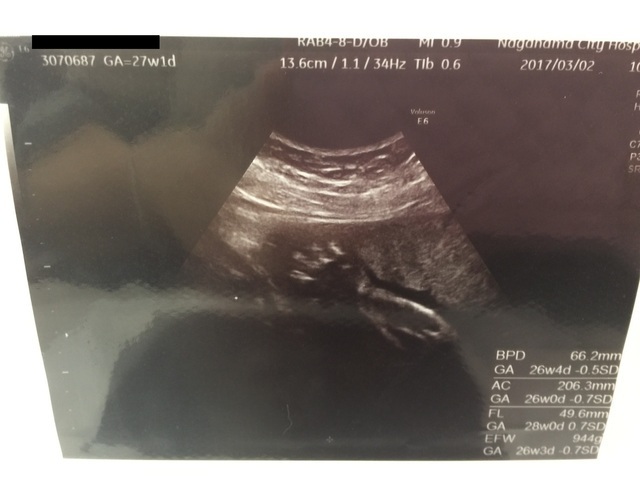

27週1日(27w1d・女の子)|mappy さん(37歳)

エコー写真撮影時のエピソード:

切迫流産になり絶対安静だった日々がようやく安静解除になった検診で撮ったエコー。

病院が3Dしかなかったので、わかりにくい写真ばっかりたったのが、赤ちゃんらしい写真がようやく撮れた一枚でうれしかったです。